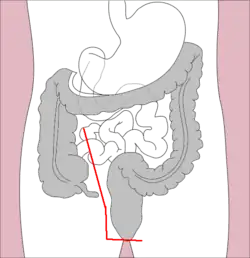

Proctocolectomy is the surgical removal of the entire colon and rectum from the human body, leaving the patients small intestine disconnected from their anus.[1] It is a major surgery that is performed by colorectal surgeons, however some portions of the surgery, specifically the colectomy (removal of the colon) may be performed by general surgeons.[2] It was first performed in 1978 and since that time, medical advancements have led to the surgery being less invasive with great improvements in patient outcomes.[3] The procedure is most commonly indicated for severe forms of inflammatory bowel disease such as ulcerative colitis and Crohn's disease. It is also the treatment of choice for patients with familial adenomatous polyposis.[4]

The surgical removal of the entire colon and rectum is a major surgery with many complex steps involved. In brief, the surgeon will begin by making an incision in the patient’s belly and then expose the colon (large intestine). They will then remove the entire large intestine being careful not to damage any other nearby internal organs.[9] Next the surgeon will remove the patient’s rectum. Lastly the surgeon will connect the patient’s small intestine to their anus so that they will be able continue having bowel movements from their bottom. This is known as an ileoanal anastomosis.[9] It is important to note that the surgeon preserves the patient’s anus and sphincter muscles in order to prevent fecal incontinence when the small intestine is connected to the anus.[10]